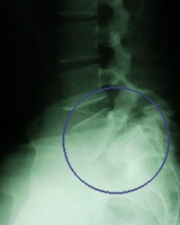

Флебография

Флебографията (от phlebos-вена и graphos-изобразявам) представлява рентгеново изследване на вените с...